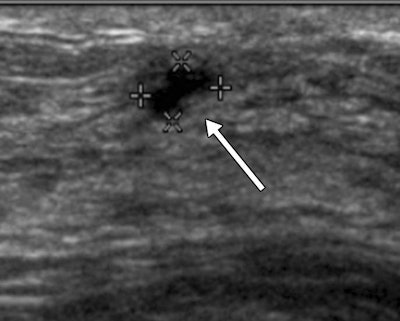

Out of 2,662 trial participants recruited between 2004 and 2006, 519 (19.5%) had 745 BI-RADS 3 lesions on ultrasound, representing 25% of all ultrasound-detected lesions in the study, according to the authors. Of these lesions, 124 (16.6%) were biopsied, and six of these biopsied lesions were malignant (representing 0.8% of BI-RADS 3 lesions). The average size of the detected cancers among the BI-RADS 3 lesions was 10 mm.

During follow-up imaging at six months, suspicious changes were observed in only one of the 745 lesions characterized as BI-RADS 3. At 12-month follow-up, suspicious changes were observed in a second BI-RADS 3 lesion, revealing an invasive breast cancer that had not yet spread beyond the breast.